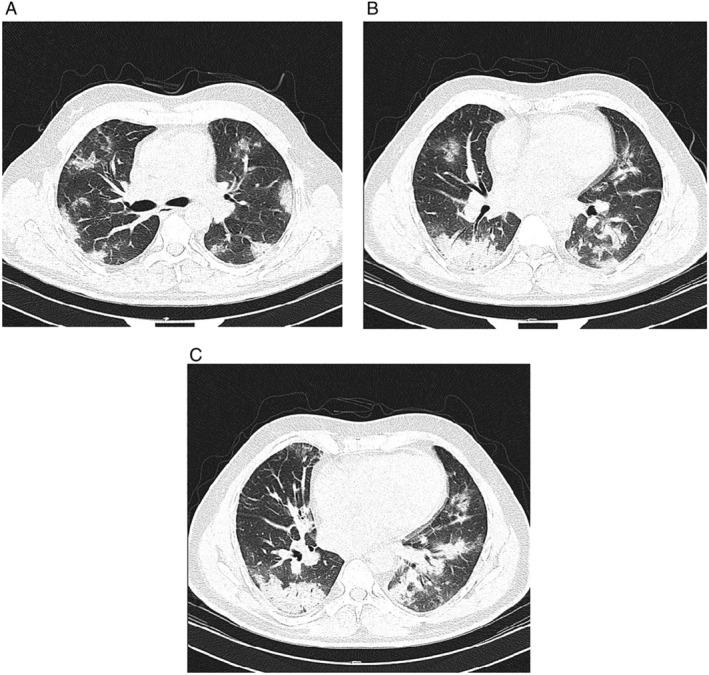

The impact of severe acute respiratory syndrome coronavirus 2 (SARS-CoV-2) on diastolic function is less known. We describe a 46-year-old man with a history of mild hypertension who presented to the emergency department with fever, cough, and myalgia for 2 days. The patient was tested positive for SARS-CoV-2. He was admitted and started on a combination of antiviral and antimicrobial therapy. He developed respiratory distress 2 days later, and O saturation declined. Blood tests showed an increased N-terminal pro-B type natriuretic peptide (NT-proBNP) level, and echocardiography showed normal left ventricular ejection fraction and E/e' ratio of 16. Computed tomography scan showed interstitial pulmonary oedema and prominent peripheral pulmonary vascular markings. Given these findings, heart failure with preserved ejection fraction (HFpEF) was considered. Low-dose diuretic was started, and fluid administration was restricted, resulting in a decrease in NT-proBNP level, clinical and haemodynamic stabilization, and improved oxygenation. This case highlights the occurrence of HFpEF in coronavirus disease 2019.

严重急性呼吸综合征冠状病毒 2(SARS-CoV-2)对舒张功能的影响知之甚少。我们描述了一位 46 岁的男性患者,有轻度高血压病史,因发热、咳嗽和肌肉疼痛 2 天就诊于急诊科。该患者 SARS-CoV-2 检测呈阳性。他被收治入院,并开始接受抗病毒和抗菌药物联合治疗。2 天后,他出现呼吸窘迫,血氧饱和度下降。血液检查显示 N 末端脑利钠肽前体(NT-proBNP)水平升高,超声心动图显示左心室射血分数正常,E/e' 比值为 16。计算机断层扫描显示间质性肺水肿和明显的外周肺血管标记。鉴于这些发现,考虑心力衰竭伴射血分数保留(HFpEF)。开始给予小剂量利尿剂,并限制液体输入,导致 NT-proBNP 水平下降,临床和血液动力学稳定,以及氧合改善。本病例强调了 COVID-19 中 HFpEF 的发生。